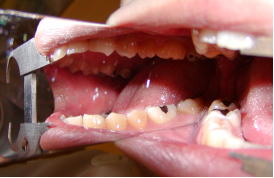

(1)開口障害を認める症例

@開口度

1)正常開口度---切歯間距離が38mm以上を言います。

2)開口障害---開口度25mm以下

開口度が2cm医科になると、ラバーがかかりにくい 、タービン、エンジンが入らないという状態になります。

3)強度開口障害---開口度10mm以下

ほとんどの歯科治療が不可能になります。

A開口障害と歯科治療

ショートのバーと、ショートヘッドのハンドピースを使用します。

開口器の使用は最小限にとどめ、休みをとりながら歯科治療を行います。

上から、22mm、18mmのタービン 上から、14mm、13mm、9mmのタービン。